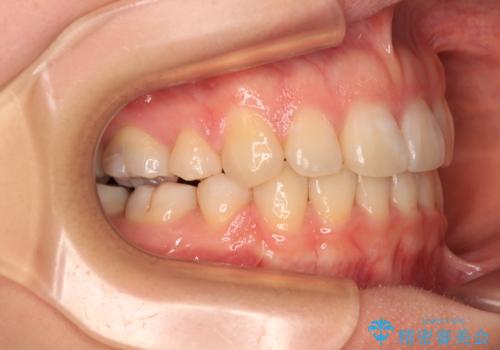

- 口元の突出感を気にして来院された患者様です。

口元を積極的に引っ込めるために、上下左右の第一小臼歯を4本抜歯することとし、ワイヤー装置による矯正治療を行うこととしました。

上下前歯がくちばしのように突出していましたが、抜歯矯正により口元が引っ込み、唇が閉じやすくなり、鼻の下の膨れた感じも解消されました。